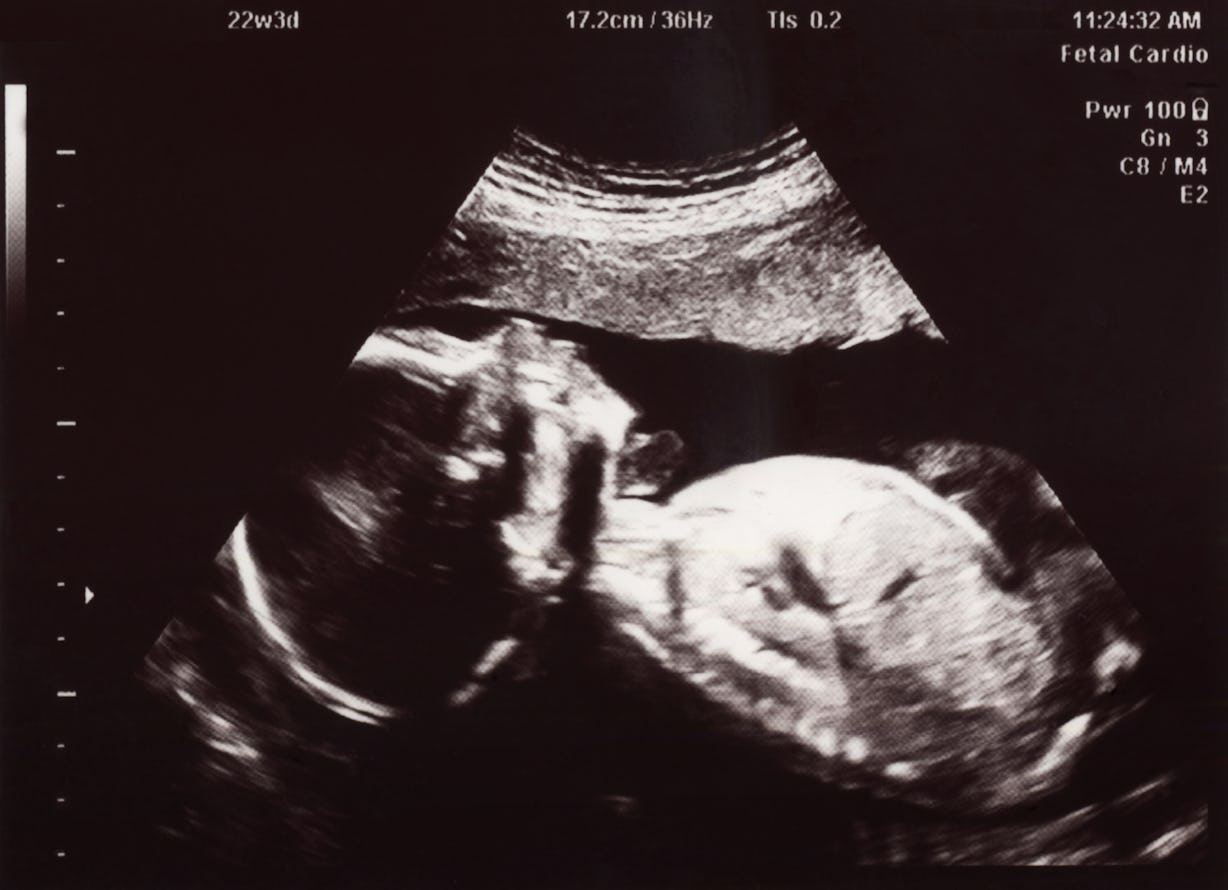

Can Baby Breathe Without Amniotic Fluid . This liquid will protect the baby from external. This “inhalation” is more like a swallowing movement. During weeks 10 and 11 of pregnancy, the developing baby inhales tiny bits of amniotic fluid. Instead, the umbilical cord provides the baby with oxygen until the first breath after. We looked up the new word. A fetus needs some amniotic fluid in the uterus to survive. Even though your baby won't breathe on their own until birth, they begin taking practice breaths as early as 10 weeks by inhaling and exhaling small amounts of amniotic fluid. This process is essential for lung development and It helps the baby’s lungs as they begin. Amniotic fluid starts to collect in the sac after ten or twelve days of conception. Once your baby’s lungs are fully developed, they still cannot breathe in the womb as they are surrounded by amniotic fluid and their lungs are. Can a baby live without amniotic fluid? Babies don’t truly breathe in the womb. However, the exact amount of. With no fluid, our baby would develop no strength in its lungs and would only survive his birth by minutes or hours.